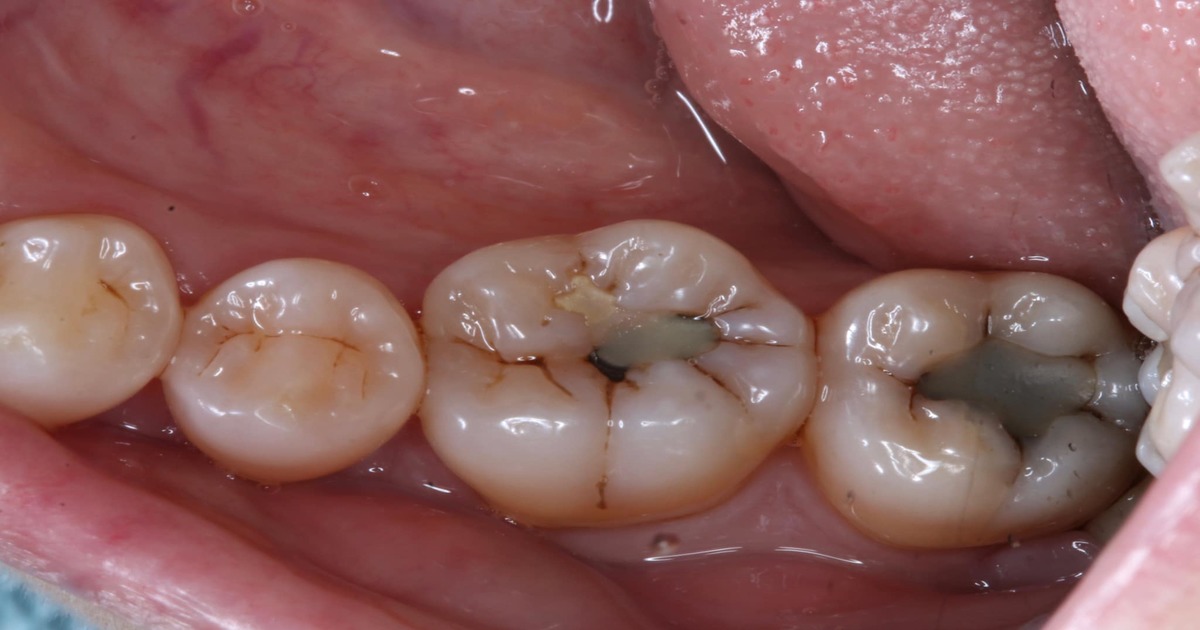

کیا آپ کے دانتوں میں بھی کیڑا لگنے کی وجہ سے سوراخ ہوگیا ہے؟ تو بتائے گئے طریقے کو آزمائیں اور دانتوں کی فلنگ کو بھول جائیں

اکثر ہم کھانا کھا کر سوجاتے ہیں اور برش نہیں کرتے تو منہ اور دانتوں میں کھانا رہ جاتا ہے جو بیکٹریا بن کر دانتوں میں چپک جاتا ہے اور جس کی وجہ سے دانت کالے ہونے لگ جاتے ہیں اور ان میں کیڑے لگ جاتے ہیں جو آپ کو شدید تکلیف میں مبتلا کردیتے ہیں اور ایسی صورتحال میں دانت میں سوراخ ہوجاتا ہے اور کھانا اس میں پھنس جاتا ہے جو آپ کی تکلیف میں اضافہ کردیتا ہے۔ اس لیے صبح اور رات کو سونے سے پہلے برش لازمی کریں۔

دانت میں سوراخ ہونے کی صورت میں کیا کیا جائے؟

ان سوراخ کو بھرنے کے لیے ضروری ہے کہ ایسی غذاؤں کا استعمال کریں جس میں کیلشیم ، میگنیشیم ، فیٹی ایسڈ ، پروبائیوٹکس پائی جاتی ہوں کیونکہ ایسی چیزیں دانتوں کو صحت مند بنانے میں کافی مددگار ثابت ہوتی ہیں ۔

اس کے لیے روزانہ رات کو دودھ کا استعمال کریں اور دن میں کم از کم ایک بار دہی ضرور کھائیں کیونکہ ان میں کیلشیم اور میگنیشیم کی بھاری مقدار پائی جاتی ہے ۔ ان کے استعمال سے دانتوں کے سوراخ کچھ ہی دن میں بھرنے لگیں گے اور آپ کو دانتوں کی تکلیف دہ فلنگ نہیں کروانی پڑے گی۔